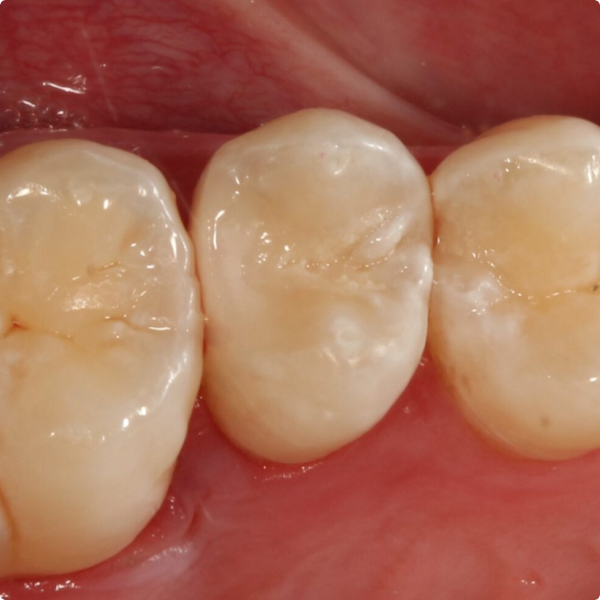

The patient reported no postoperative sensitivity, and no complications emerged. Because the patient is considered higher risk for future dental issues, Dr Shankla scheduled a follow-up X-ray in one year to assess the restoration’s durability.

From the patient’s viewpoint, the streamlined two-step process and shorter chair-time contributed to a more pleasant treatment visit. For the clinician, the workflow gains were significant: replacing what would normally be a multi-stage, technique-sensitive procedure with a rapid, reliable alternative.

The case helped highlight how Stela can transform restorative practice and deliver efficient, high-quality, durable and aesthetic results with minimal complexity.